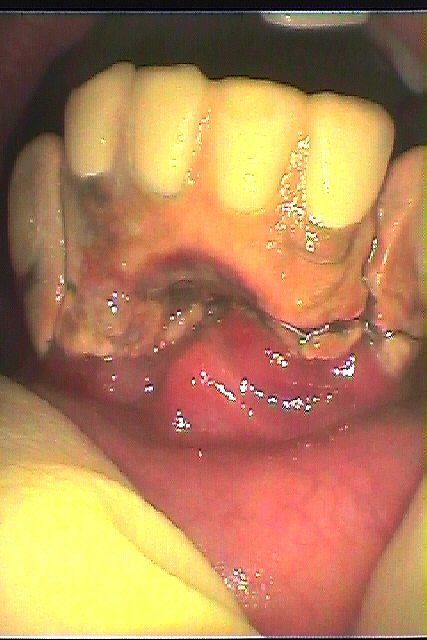

ブログ一覧|広島市安佐南区の歯科医院 ブログ一覧 トップ ブログ一覧 お知らせ スタッフブログ ブログ一覧 お知らせ 2019/04/04 下前歯のインプラント埋入 最終補綴へ お知らせ 2019/04/03 下顎前歯部のインプラント埋入 かなりむつかしい部位にもなります お知らせ 2019/04/03 下顎のインプラント埋入 下顎義歯の安定をインプラントにて図りたい 総入れ歯は安定しなく噛めない お知らせ 2019/04/02 銀歯を外していきます この下に虫歯があります お知らせ 2019/04/02 インプラントなしのジルコニアブリッジの作成 強度も高く審美性も兼ね備えたきれいなブリッジを作成していきます お知らせ 2019/04/02 銀歯を外して、根の治療からセラミック治療を行います お知らせ 2019/04/01 右下6番のセラミック治療 虫歯治療から白いきれいな歯へ お知らせ 2019/04/01 その後のインプラントの経過 << 1 2 3 4 5 … 420 421 422 423 424 … 870 871 872 873 874 >> Web診療予約 初めての方へ 選ばれ続ける理由 院内設備について 歯が痛いしみる一般歯科 歯がぐらぐらする歯周病 健康な歯を保ちたい予防歯科 子供の虫歯予防をしたい小児歯科 銀歯をセラミックに審美歯科 白い歯を目指しませんか?ホワイトニング 矯正専門医がいるので安心矯正歯科 抜けた歯を補いたいインプラント・入れ歯 医院案内 スタッフ紹介 メリィハウス歯科クリニックオフィシャルホームページ ラベンダー歯科クリニックオフィシャルホームページ お知らせ・ブログ ホーム 診療科目 一般歯科 歯周病治療 予防治療 小児歯科 審美治療 ホワイトニング 矯正歯科 入れ歯・インプラント マウスピース矯正 初めての方へ 院長・スタッフ 設備紹介 医院案内・アクセス メニューを閉じる